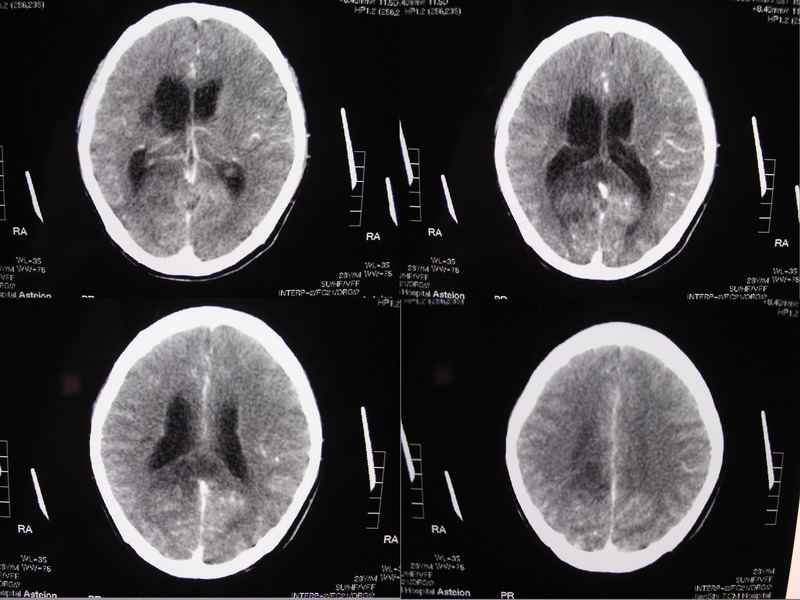

以下是引用余辉在2007-5-14 17:03:00的发言:[br]右侧脑室颞极后方可见高密度块状影,颞极呈杯口状推挤前移,右侧大脑脚及丘脑上部受推挤向对侧移位,右丘脑区结构紊乱,增强扫描病灶有不规则强化,以下部颞极后方为著。胼胝体压部及右枕叶视辐射区低密度改变,右基底节区低密度改变,双侧脑室不对称积水征象,意见:1颞极后方—右丘脑区占位性病变,如室管膜瘤等2脑血管疾病如moyamoya,局部脑血管畸形等3脑膜炎等后遗改变,建议mr及脑血管造影检查[br][br][本贴已被 余辉 于 2007-5-14 17:05:26 修改过]

以下是引用千里草在2007-5-14 15:54:00的发言:[br]考虑:1、双侧梗阻性脑积水;[br] 2、右侧基底节区缺血性脑血管疾病。

以下是引用qiuleiyu在2007-5-14 18:43:00的发言:[br]支持;1,交通性脑积水(病脑后遗征?)2,右基底节及胼骶体压部低密度灶伴轻度占位表现,结合年龄考虑moyamoya,建议dsa.[br]